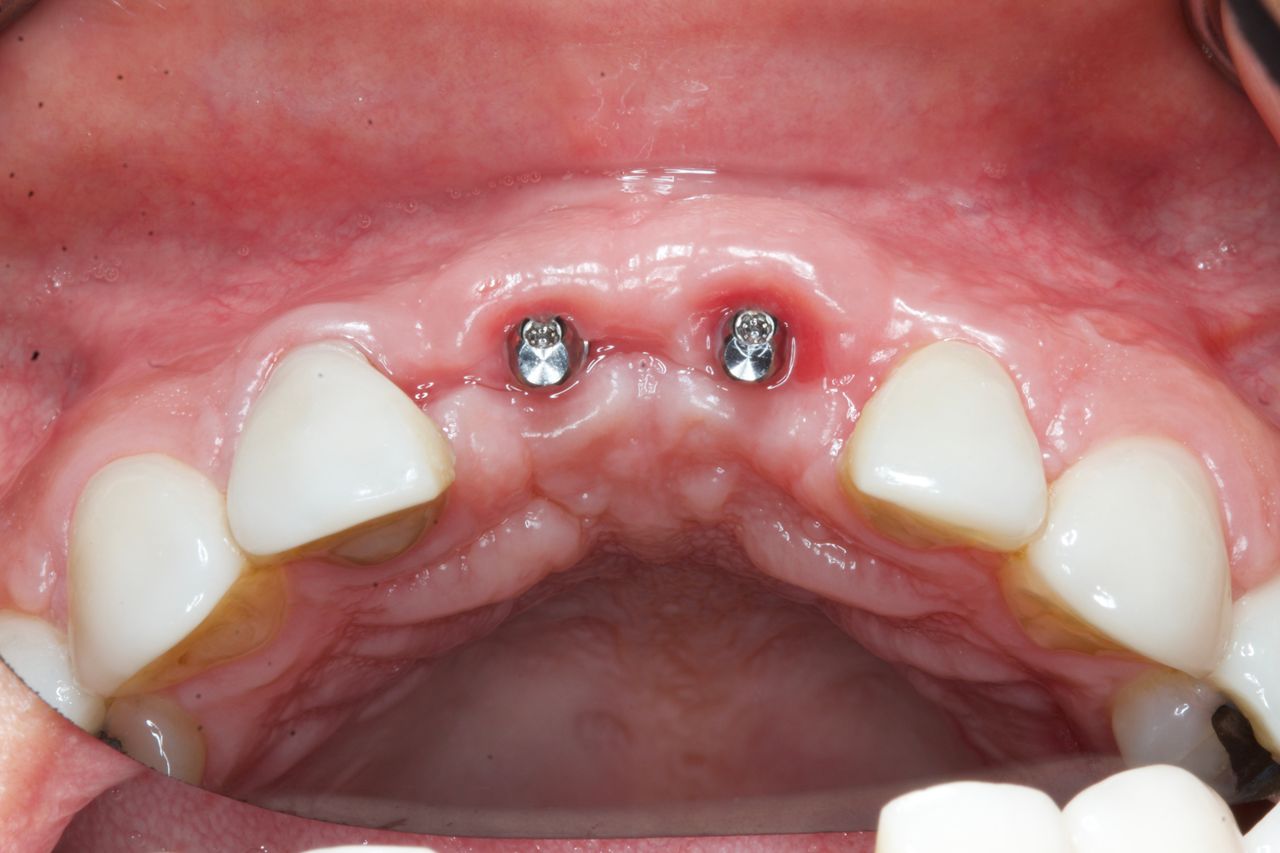

¿Que es un Implante Dental?

- Es un aditamento con forma de tornillo elaborado de titanio o de zirconio, que se inserta en el hueso a través de una pequeña cirugía, hasta que se osteointegre con el hueso y se coloque un provisional y posteriormente una corona definitiva.

-La ventaja de los Implantes Dentales es que sustituyen a los dientes o muelas perdidos sin que se tenga que desgastar los dientes adyacentes para un puente fijo.